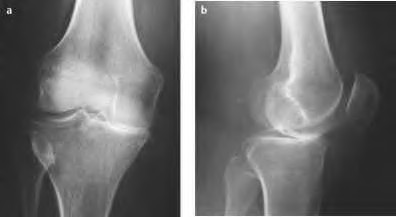

A 52-year-old male with isolated medial compartment osteoarthritis is evaluated for a unicompartmental knee arthroplasty (UKA).

Which of the following conditions is considered a strict contraindication to a traditional mobile-bearing UKA?